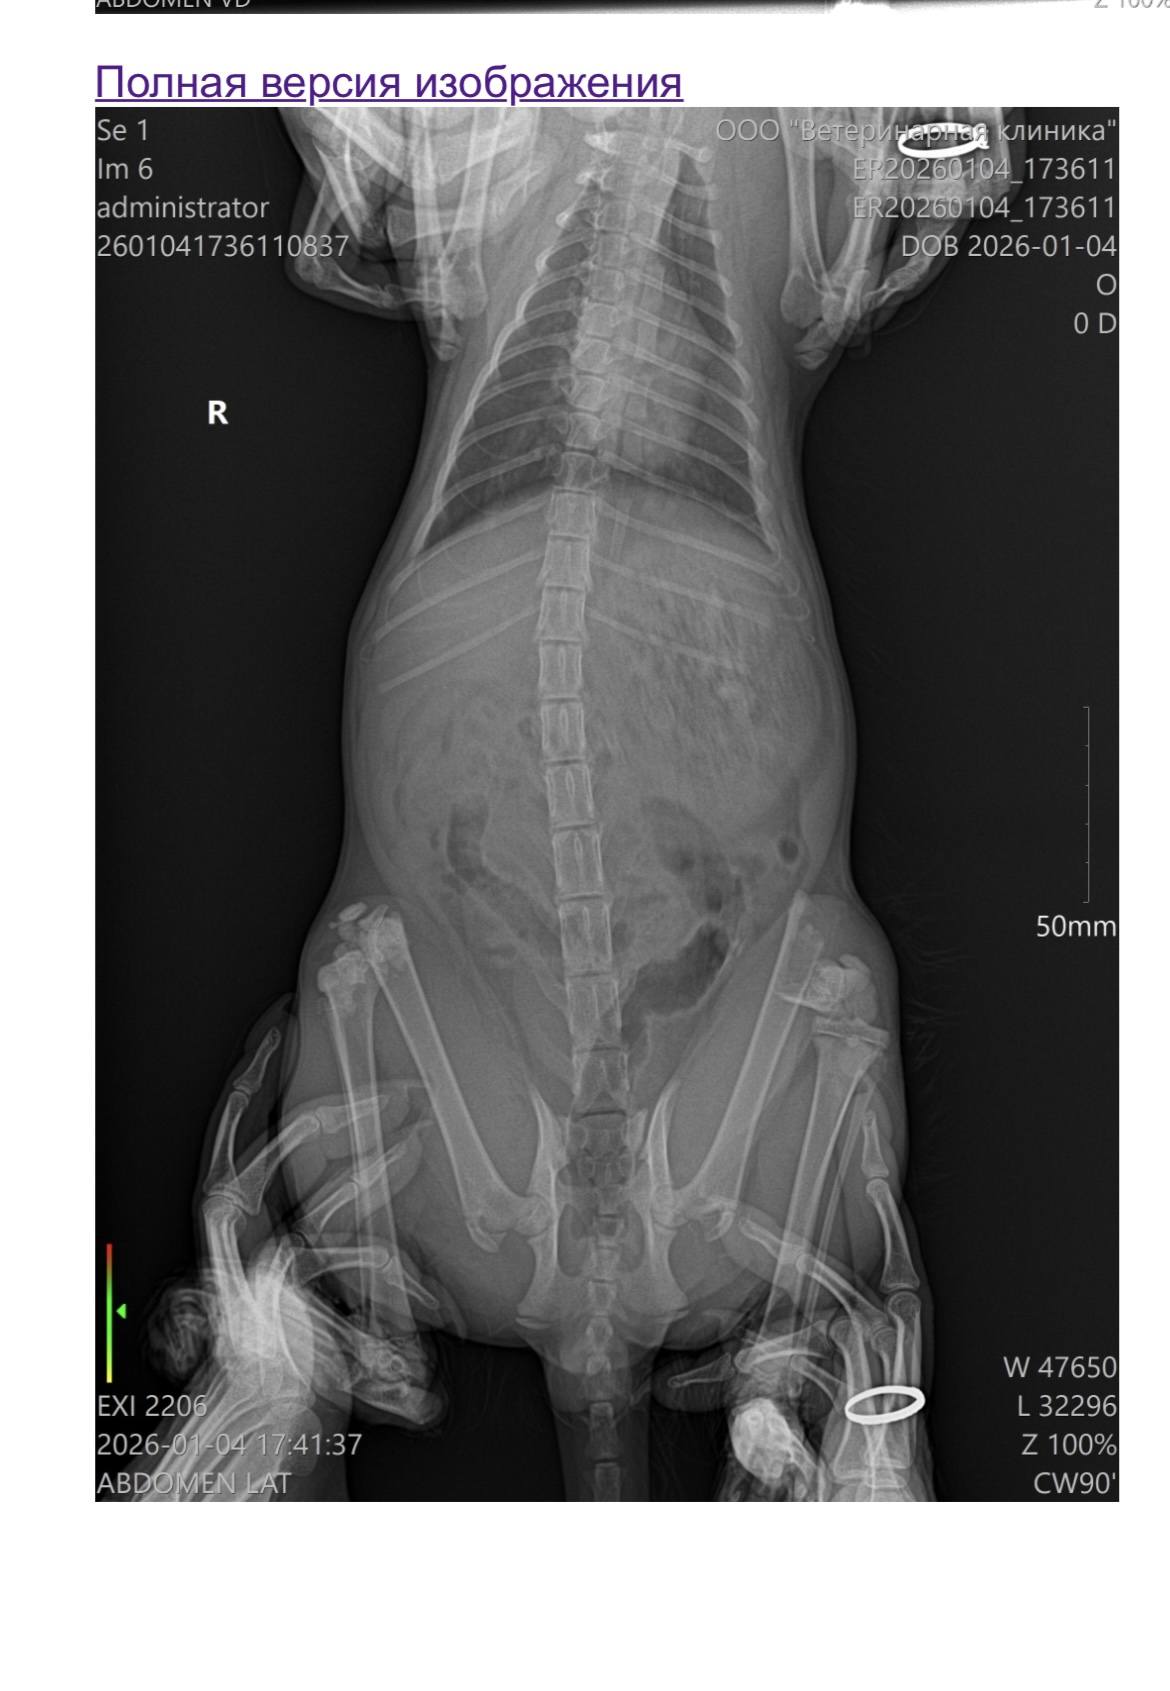

Подобрали кота с улицы, к сожалению, по стечению обстоятельств, маленький выпал с 7-го этажа, перелом блоков бедренных костей, котик еще совсем молодой , предположительно 4-6 месяцев, нужно вставлять спицы, взяли его совсем недавно но очень прикипели с сыном к нему, стоимость операции и реабилитации около 80-и тысяч. Самостоятельно, к сожалению, не могу найти средства, т.к недавно уволилась с работы, живу вдвоем с сыном, отец сына не принимает участия, помогает мамуля, но у и нее нет таких денег в данный момент, чтоб сделать операцию , надеюсь на чудо